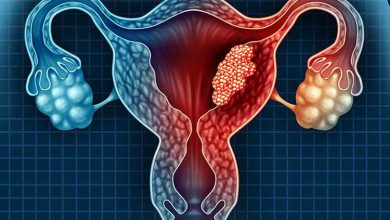

فشار خون در بارداری

فشار خون بالا در بارداری میتواند علامت یا عاملی برای ایجاد مشکلاتی در مادر و جنین باشد. برای درمان فشار خون بالا در بارداری میتوانید از راههای زیر استفاده کنید:

- داروهای تجویز شده توسط پزشک را به موقع مصرف کنید. برخی از داروهای فشار خون قدیمی سبب ایجاد مشکلاتی در زنان باردار میشوند. در ادامه بهترین قرص درمان فشار خون بالا به شما معرفی می کنیم .بر اساس گزارش کلینیک MAYO از داروهای پایین آورنده ی فشار خون شامل موارد زیر باید جدا خودداری کرد:

این داروها از طریق جریان خون به جنین میرسند و در رشدش تاثیر گذاشته و میتوانند اثر منفی بر سلامت جنین داشته باشند. داروهای فشار خون ذکر شده همچنین سبب کاهش مقدار خون مادر نیز میشوند که به توانایی بارداری مادر لطمه میزند. متیل دوپا و Labetalol داروهایی هستند که از نظر کنترل فشار خون بی خطر در نظر گرفته شده اند.

اگر در طی دوران بارداری فشار خونتان بالا میرود، در مورد نحوه ی درمان فشار خون حاملگی با دکتر فشار خون مشورت کنید.